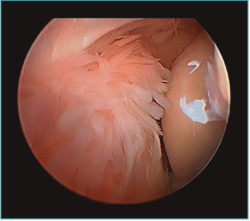

Acto seguido, realizamos nuestra secuencia de trabajo descrita anteriormente (visualización, creación de espacio, trabajo óseo y trabajo de partes blandas). El fresado óseo debe realizarse siempre con el instrumental motorizado orientado hacia el húmero, para evitar las lesiones de partes blandas. El uso de fresas o el sinoviotomo en modo no oscilante y a alta velocidad nos permitirá eliminar los osteofitos que interfieran con la movilidad, especialmente aquellos que ocupan la fosa radial o coronoidea (Figura 8). También es frecuente tener que eliminar osteofitos que aumentan la altura de la coronoides (Figura 9). Una vez eliminado el material óseo (Figura 10), flexionamos el codo para comprobar el aumento de flexión conseguido, que no será completo hasta que liberemos la cápsula posterior y la banda posterior del ligamento colateral medial. Como último paso en la cámara anterior, procedemos a la eliminación de la cápsula articular. Introducimos un Basket recto desde el portal anteromedial y vamos mordiendo la cápsula, atrapándola, cortándola y realizando un movimiento de batido hacia proximal para separar el fragmento capsular de las partes blandas anteriores. Progresamos lateralmente, descubriendo el vientre muscular del braquial anterior, hasta que aparezca tejido graso detrás de la cápsula resecada. En este momento, cambiamos los portales y miramos desde el portal anteromedial proximal y utilizamos la pinza Basket desde el portal anterolateral. Una vez realizada esta capsulotomía amplia, usamos el sinoviotomo para eliminar los restos capsulares proximales. Durante todo este proceso, utilizamos un retractor desde el portal anterolateral proximal para tensar la cápsula y proteger, sobre todo, el nervio radial, que queda situado justo en la grasa lateral al músculo braquial y anterior a la cabeza del radio, y a escasos milímetros de nuestro instrumental de trabajo; aunque no es aconsejable, es posible traccionar de él e introducirlo en la articulación con ayuda de un palpador introducido en la grasa que lo recubre. El nervio mediano se encuentra medial al músculo braquial, pero en un plano bastante más anterior, lo cual hace que esté mucho más protegido(12,13).

Figura 10. Mismo caso que en las Figuras 8 y 9 después del trabajo óseo. Obsérvese la recreación y fusión de ambas fosas radial y coronoidea con el típico aspecto de “tobogán” después del fresado de la cara anterior del húmero y la disminución de la altura de la coronoides. Todavía no se ha procedido a realizar la capsulectomía.